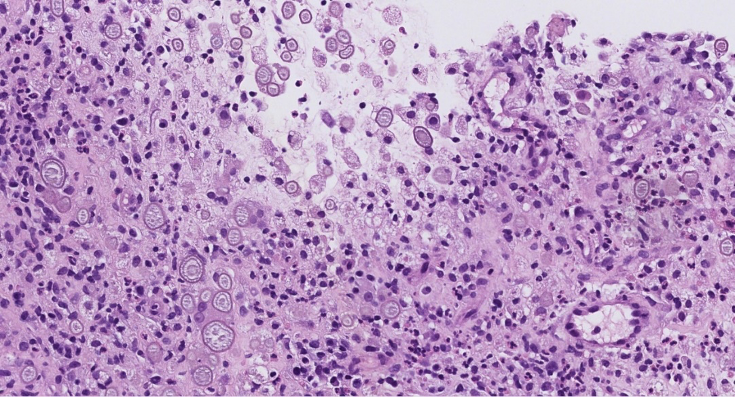

Figure 1. HE

Histologically, Liesegang rings appear as variably sized round structures with a laminated or ring-like configuration and may contain a central dense core. This pattern might result from alternating precipitation and diffusion of supersaturated solutions around a central amorphous nidus. They are typically PAS or DPAS positive and negative for calcium stains such as Von Kossa, helping to distinguish them from calcified structures.

In renal tissue, Liesegang rings may be associated with chronic inflammatory processes, including cystic lesions and xanthogranulomatous pyelonephritis. Their presence can lead to diagnostic confusion with parasitic organisms, psammoma bodies, or Michaelis–Gutmann bodies of malakoplakia.